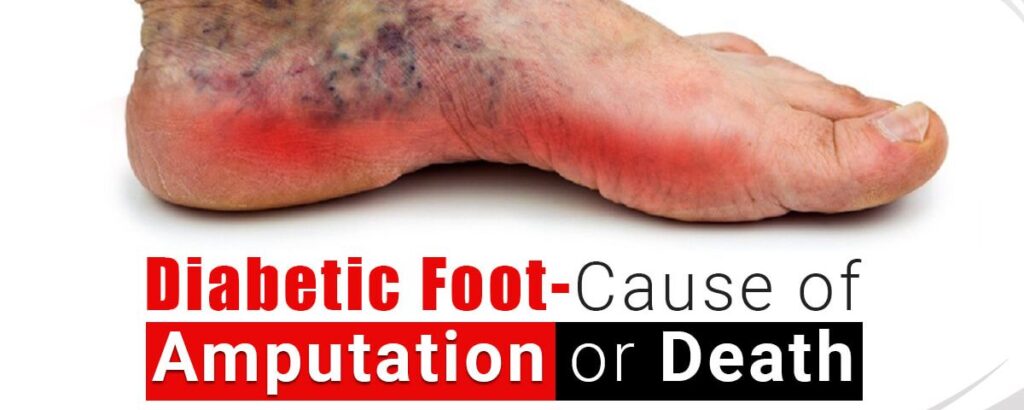

Ancaman Amputasi pada Penderita Kencing Manis akibat Diabetic Foot

Diabetes Melitus (DM) merupakan penyakit metabolik kronis yang ditandai dengan tingginya kadar gula darah akibat gangguan produksi atau kerja insulin dalam tubuh. Salah satu komplikasi serius dari DM adalah Diabetic Foot (DF) atau kaki diabetik, yaitu kondisi kerusakan jaringan pada kaki yang disebabkan oleh kombinasi neuropati (kerusakan saraf), gangguan aliran darah (iskemia), dan infeksi. Kaki diabetik menjadi masalah kesehatan yang signifikan karena dapat berkembang menjadi luka kronis yang sulit sembuh, bahkan berujung pada amputasi jika tidak ditangani dengan baik. Kondisi ini sering kali diawali dengan hal-hal sederhana seperti luka kecil, lecet, atau tekanan berlebih pada kaki yang tidak dirasakan oleh penderita akibat menurunnya sensitivitas saraf. Oleh karena itu, pemahaman tentang DM dan komplikasinya, khususnya DF, sangat penting untuk mencegah dampak yang lebih serius.

Penyebab utama terjadinya diabetic foot adalah neuropati diabetik dan penyakit pembuluh darah perifer yang sering dialami oleh penderita diabetes dalam jangka panjang. Neuropati menyebabkan hilangnya sensasi nyeri, panas, atau dingin pada kaki, sehingga penderita tidak menyadari adanya luka atau cedera. Sementara itu, gangguan sirkulasi darah menghambat proses penyembuhan luka karena jaringan tidak mendapatkan cukup oksigen dan nutrisi. Selain itu, kadar gula darah yang tinggi juga menciptakan lingkungan yang ideal bagi pertumbuhan bakteri, sehingga meningkatkan risiko infeksi. Faktor risiko lainnya meliputi kontrol gula darah yang buruk, kebiasaan merokok, penggunaan alas kaki yang tidak sesuai, serta kurangnya perawatan kaki. Kombinasi dari faktor-faktor ini menjadikan kaki sebagai bagian tubuh yang sangat rentan pada penderita diabetes.

Gejala diabetic foot dapat bervariasi tergantung pada tingkat keparahan kondisi. Pada tahap awal, mungkin hanya terlihat perubahan warna kulit, kulit kering, atau kapalan. Seiring perkembangan kondisi, dapat muncul luka terbuka (ulkus), pembengkakan, bau tidak sedap, hingga keluarnya cairan atau nanah dari luka. Pada kasus yang lebih berat, jaringan kaki dapat mengalami kematian (gangren), yang sering kali ditandai dengan perubahan warna menjadi hitam. Diagnosis biasanya dilakukan melalui pemeriksaan fisik, evaluasi saraf, serta pemeriksaan aliran darah pada kaki. Penanganan diabetic foot memerlukan pendekatan multidisiplin, termasuk kontrol gula darah yang ketat, perawatan luka yang tepat, penggunaan antibiotik jika terdapat infeksi, serta tindakan bedah jika diperlukan. Perawatan luka modern juga sering melibatkan teknik seperti debridement (pembersihan jaringan mati) dan penggunaan balutan khusus untuk mempercepat penyembuhan.

Pencegahan diabetic foot merupakan langkah yang paling efektif untuk mengurangi risiko komplikasi serius. Penderita diabetes dianjurkan untuk melakukan pemeriksaan kaki secara rutin setiap hari, menjaga kebersihan dan kelembapan kulit, serta menggunakan alas kaki yang nyaman dan sesuai ukuran. Memotong kuku dengan hati-hati dan menghindari berjalan tanpa alas kaki juga sangat penting untuk mencegah cedera. Selain itu, kontrol gula darah yang baik melalui pola makan sehat, olahraga teratur, dan kepatuhan terhadap pengobatan merupakan kunci utama dalam mencegah berbagai komplikasi diabetes, termasuk kaki diabetik. Edukasi kepada pasien dan keluarga juga memainkan peran penting dalam meningkatkan kesadaran dan kepatuhan terhadap perawatan. Dengan pencegahan yang tepat dan penanganan dini, risiko amputasi akibat diabetic foot dapat ditekan secara signifikan, sehingga kualitas hidup penderita diabetes tetap terjaga.